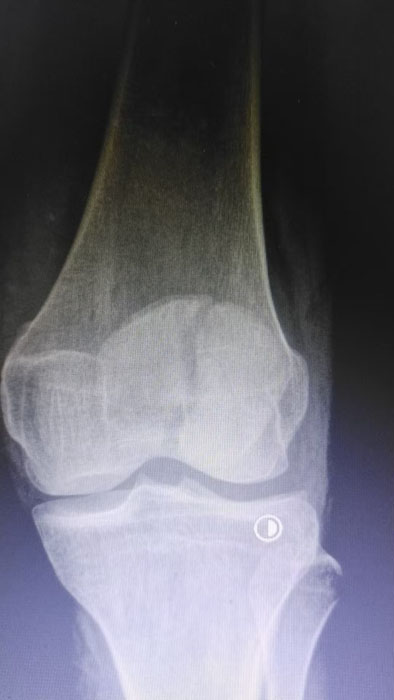

該患者因意外外傷導致髕骨骨折后,緊急前往何店鎮中心衛生院就診。該院外科醫護團隊迅速響應、規范處置,第一時間為患者完善各項術前檢查,全面細致評估患者身體狀況及骨折傷情,精準把握手術指征。為最大限度保障手術安全與治療效果,切實減少患者往返城區醫院的奔波之苦,降低就醫成本,該院立即啟動醫共體專家協作機制,正式向曾都區人民醫院申請專家技術支持。接到申請后,徐三軍主任快速響應、主動下沉,帶著豐富的臨床經驗和精湛的手術技術趕赴衛生院,與該院外科醫護團隊深入研討,結合患者具體病情制定個性化手術方案,細致梳理術前各項準備工作,為手術順利開展筑牢堅實基礎。

精湛施術 安全有序,守護患者健康

手術現場,徐三軍主任憑借多年積累的臨床經驗和嫻熟的手術技巧,精準完成骨折復位、鋼板內固定、傷口縫合等一系列關鍵操作,動作規范流暢、精準高效,最大限度減少手術創傷。該院外科醫護團隊全程密切配合、協同發力,嚴格按照手術規范操作,全程嚴密監測患者心率、血壓等生命體征,及時應對術中各類突發情況,全力保障手術安全。此次手術全程順利,術中出血量少,患者生命體征始終平穩,術后患者順利安返病房,為后續康復治療奠定了堅實基礎。